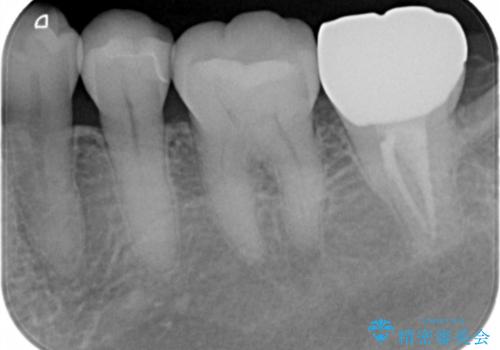

劣化して黒くなりたくない、虫歯の予防がしたいとのご希望だったのでセラミックインレー(e-maxインレー)による治療を行いました。

- e-maxインレー 7.7万円 費用は治療当時の料金となります

プラスチック樹脂は安価で治療時間も一回で終わるが歯質との隙間ができやすく虫歯の再発のリスクが高いです。また、吸水性なので何年か過ぎると劣化します。

セラミックは歯質との隙間ができにくく虫歯の再発のリスクをさげ劣化防止にもなります。